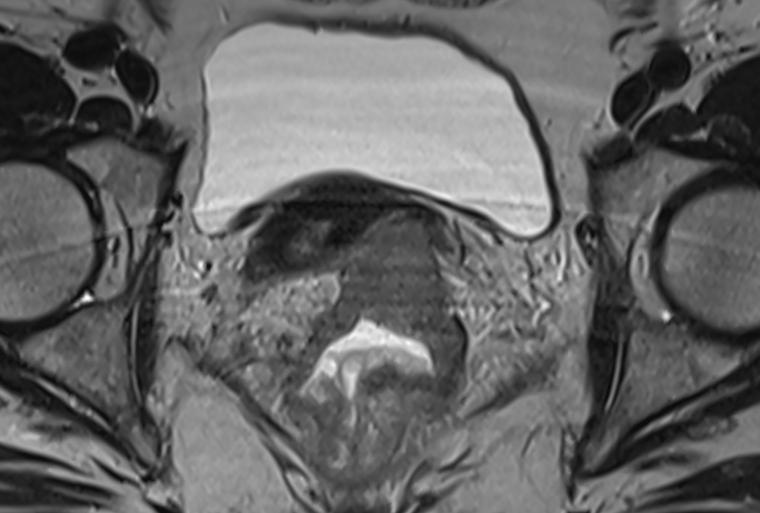

Magnetic resonance imaging (MRI) can spare patients with rectal cancer from surgery by identifying those who can "watch and wait," new research from the School of Medicine suggests.

The findings, from UVA Cancer Center’s Arun Krishnaraj, MD, MPH, and collaborators, indicate that MRI can predict patient outcomes and the risk of the tumor recurring or spreading for patients who have undergone chemotherapy and radiation.

That information could be extremely useful in determining the best course of treatment and deciding whether a patient can avoid surgery in favor of a “watch and wait” approach, the researchers say. In watch-and-wait, doctors continue to monitor patients for cancer reccurrence or spread, holding off on surgery but potentially leaving them uncertain and anxious about the future.

To help patients make the best choices and get the best outcomes, Krishnaraj and his collaborators wanted to see if MRI could serve as a crystal ball for the effects of watch-and-wait. To do this, they analyzed the results of the Organ Preservation in Rectal Adenocarcinoma (OPRA) trial to see how MRI results aligned with patient outcomes. In total, they reviewed outcomes from 277 patients, with an average age of 58, who had the stage of their rectal cancer determined by MRI. The average length of the follow-up period was slightly more than 4 years.

After crunching the numbers, the researchers determined MRI was an effective tool for predicting the patients’ overall survival, the risk of their cancer returning and their chances for keeping their bowel intact.